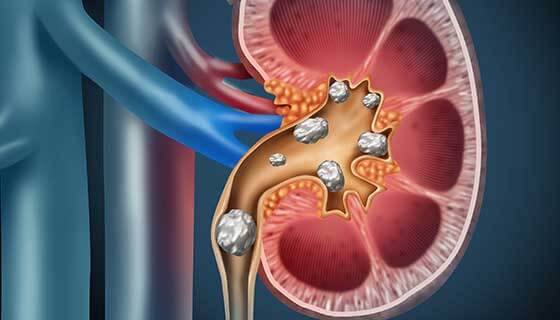

تكلفة عملية المنظار المرن تختلف من مكان لآخر وعلى حسب الإمكانيات التي يتم استخدامها في العملية، حيث أنها هي عبارة عن تقنية حديثة يتم استعمالها من أجل التخلص من حصوات الكلى بدون أي جراحة ويعتبر الإفراط في تناول الأغذية وكذلك ارتفاع درجات الحرارة العالية في الجو عبارة عن سببين أساسيين في ارتفاع نسبة الإصابة بحصى الكلى.

عندما يتم استخراج حصوات الكلية من خلال الجلد فهو عبارة عن إجراء يستخدم لإزالة حصوات الكلى من الجسم عندما يتعذر مرورها من تلقاء نفسها ويتم إدخال منظار عبر شق صغير في الظهر لإزالة حصوات الكلى.

في العادة ما يتم إجراء استخراج حصاة الكلية للحصوات الأكبر حجمًا أو عندما لا تنجح أو تتعذر الإجراءات الأخرى، مثل تفتيت الحصاة بصدمة الموجات الموجهة من خارج الجسم أو منظار الحالب.